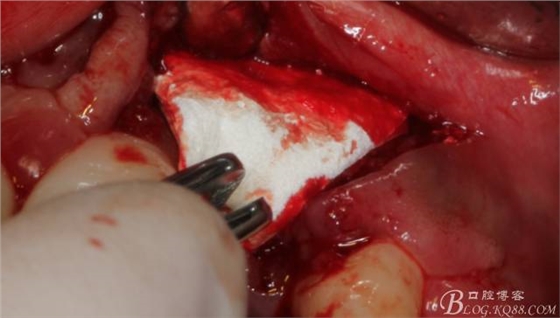

有老師問我,為什么不在此時同期植骨同期植入植體?我的觀點是:不要一次做太多事情,做得越多風(fēng)險越高。再說,此時軟組織不健康,沒有健康的軟組織如何能保證GBR的成功?所以,我僅放了一塊膠原蛋白就縫上了。